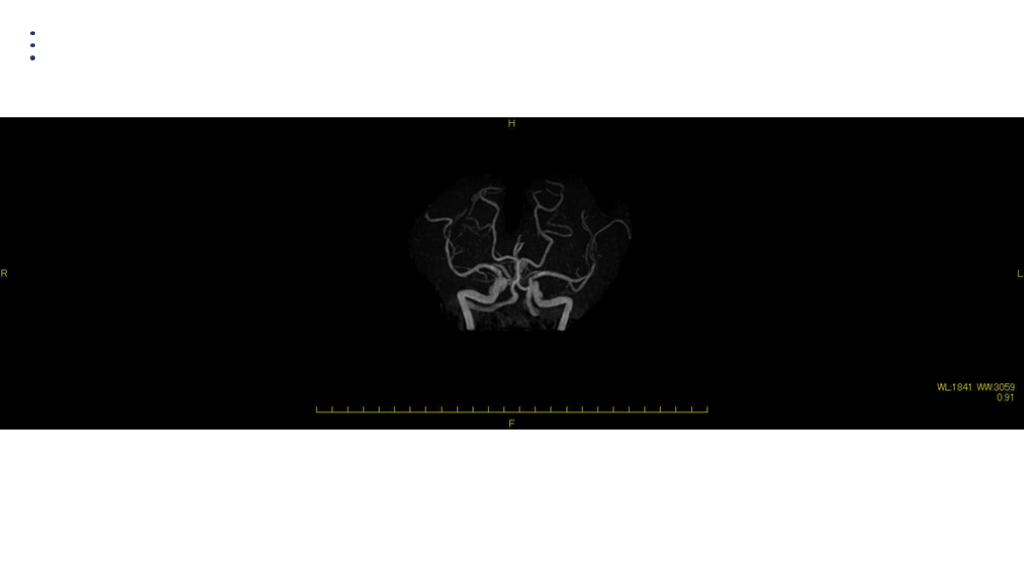

画像 所見 DAY 14 MRA 悪化